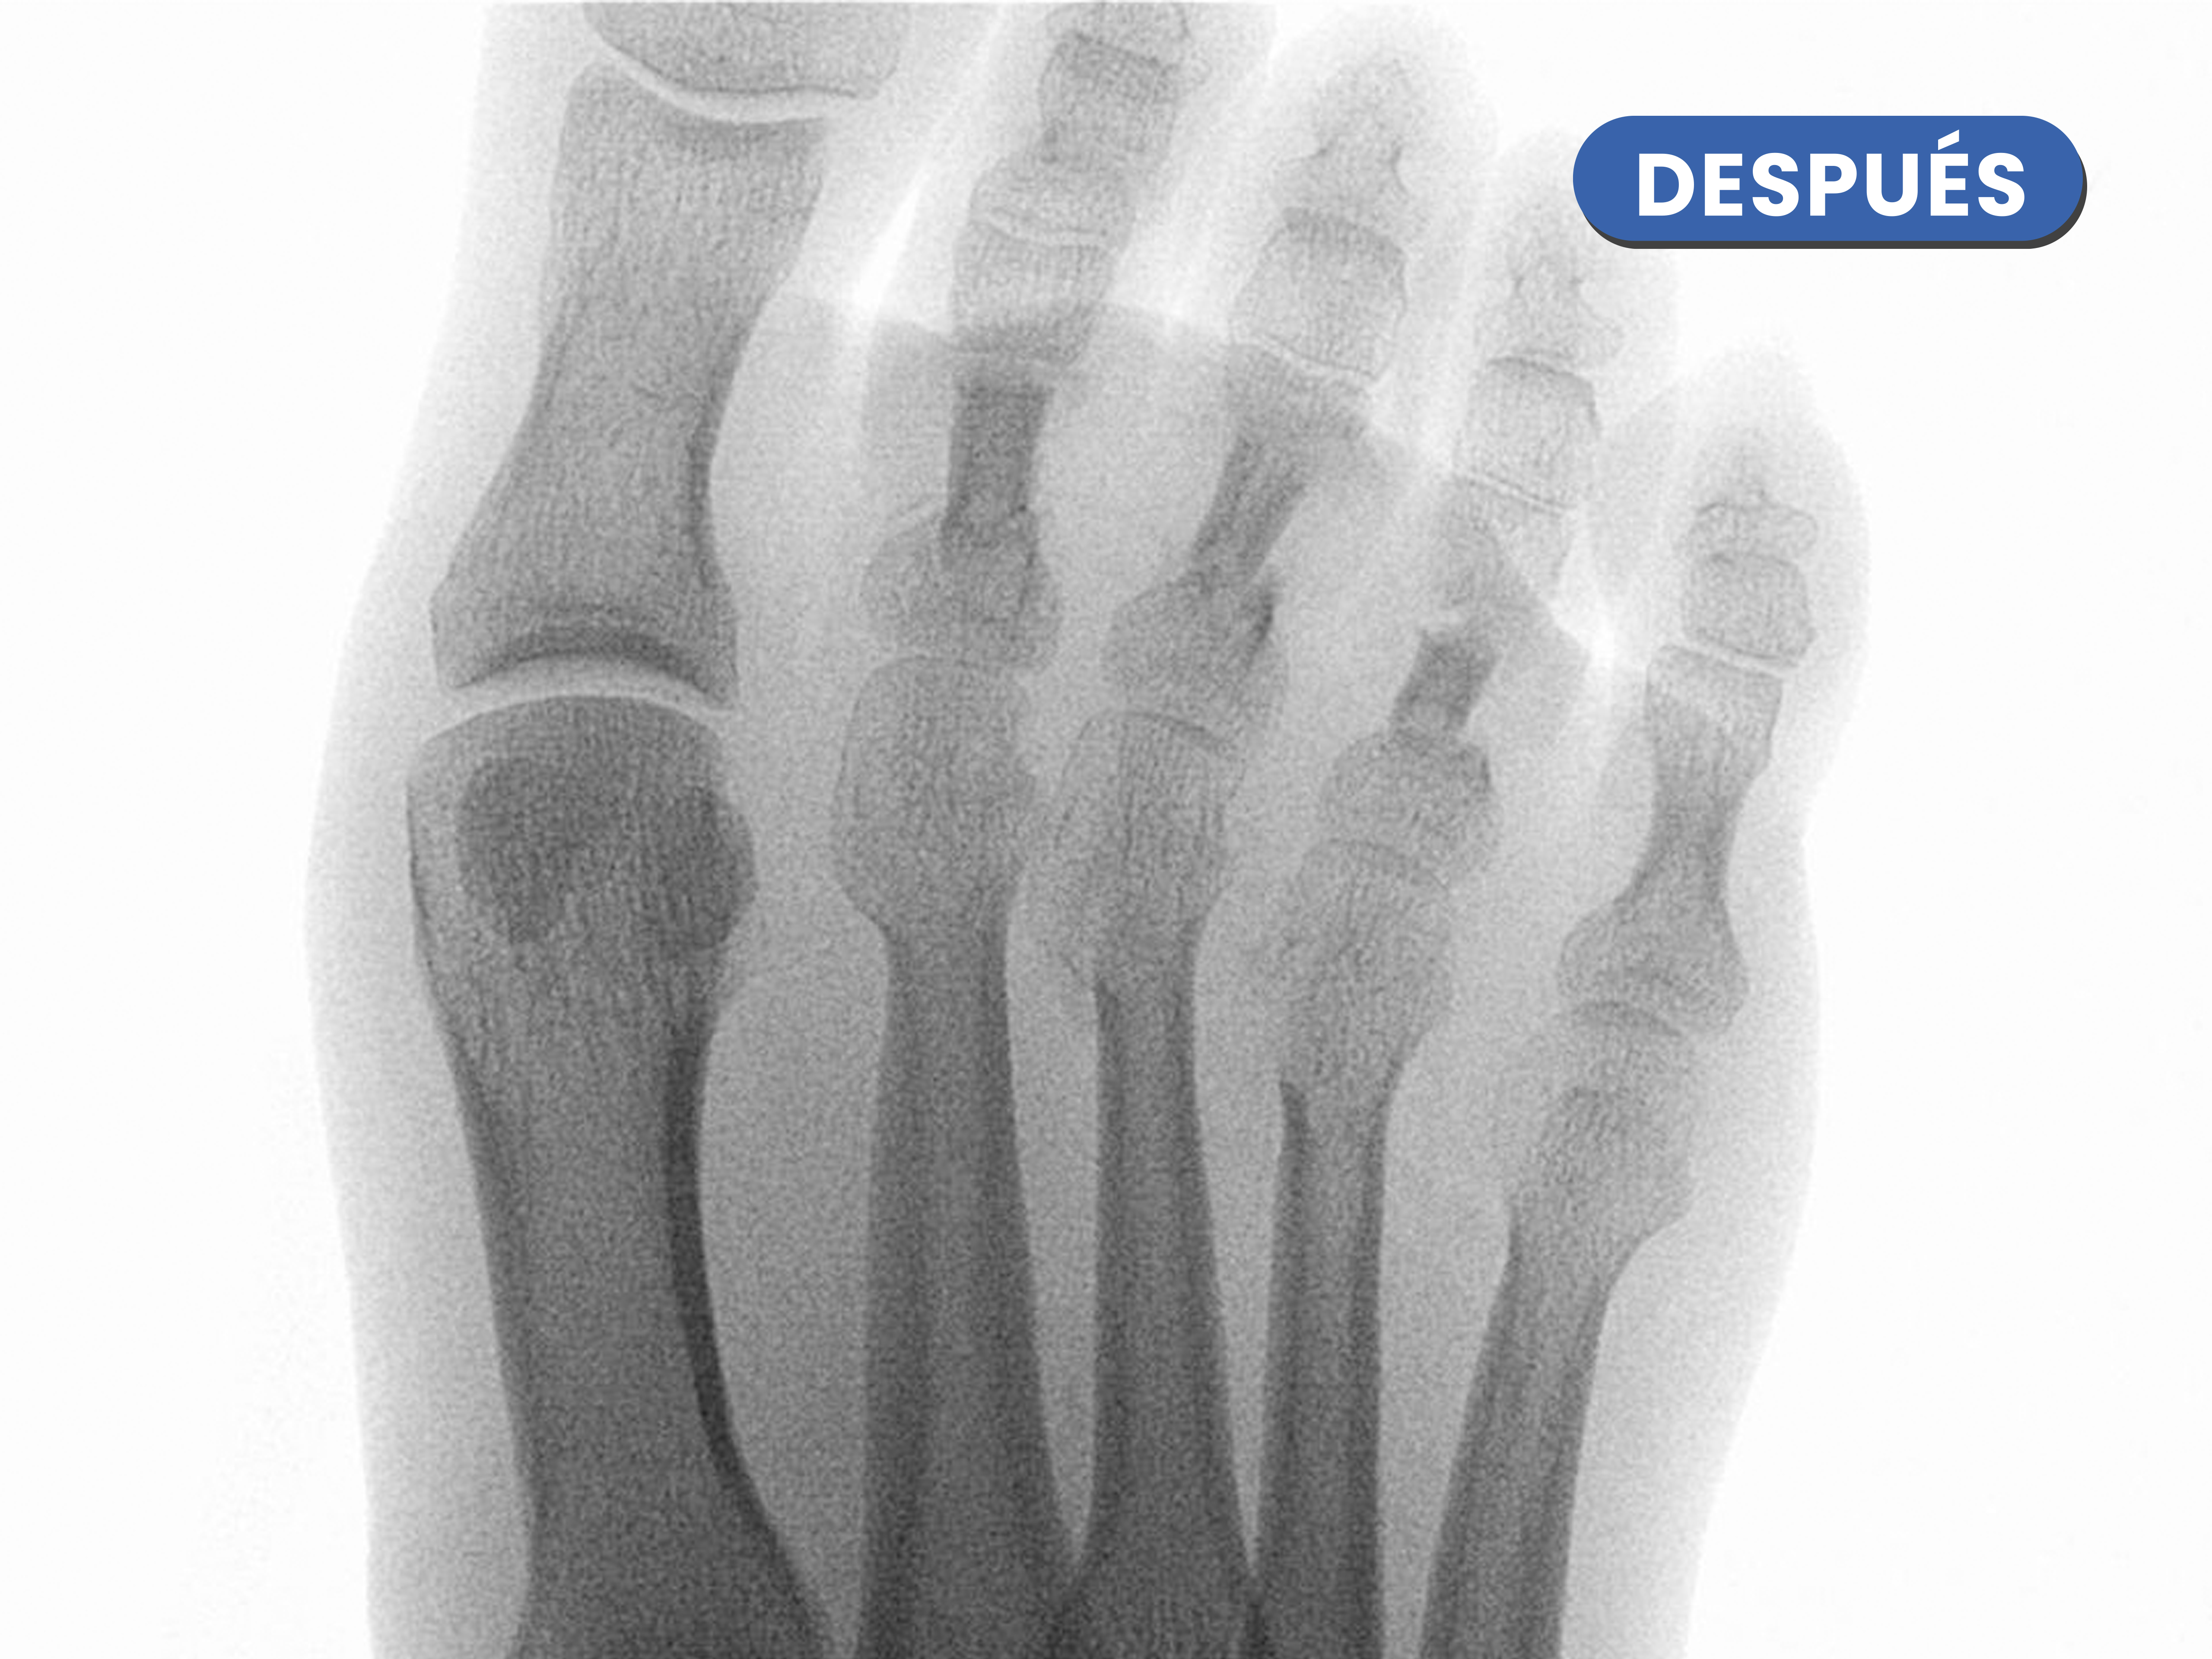

Casos reales resueltos con Cirugía de Mínima Incisión (CMI)

Te mostramos casos reales resueltos mediante cirugía de mínima incisión por el Dr. Rubén Lorca y su equipo.

Mueve las flechas para visualizar el antes y después.

Se puede observar las osteotomía cuando realizamos operatoriamente tracción de los dedos, las osteotomías realizadas justo en el cuello del metatarsiano, se visualizan de manera completa y al caminar se produce un reajuste de la carga en la zona.